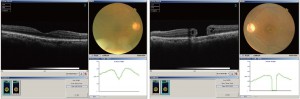

下の右図が黄斑円孔です.左図の黄斑は正常です.(光干渉断層計(OCT)検査)